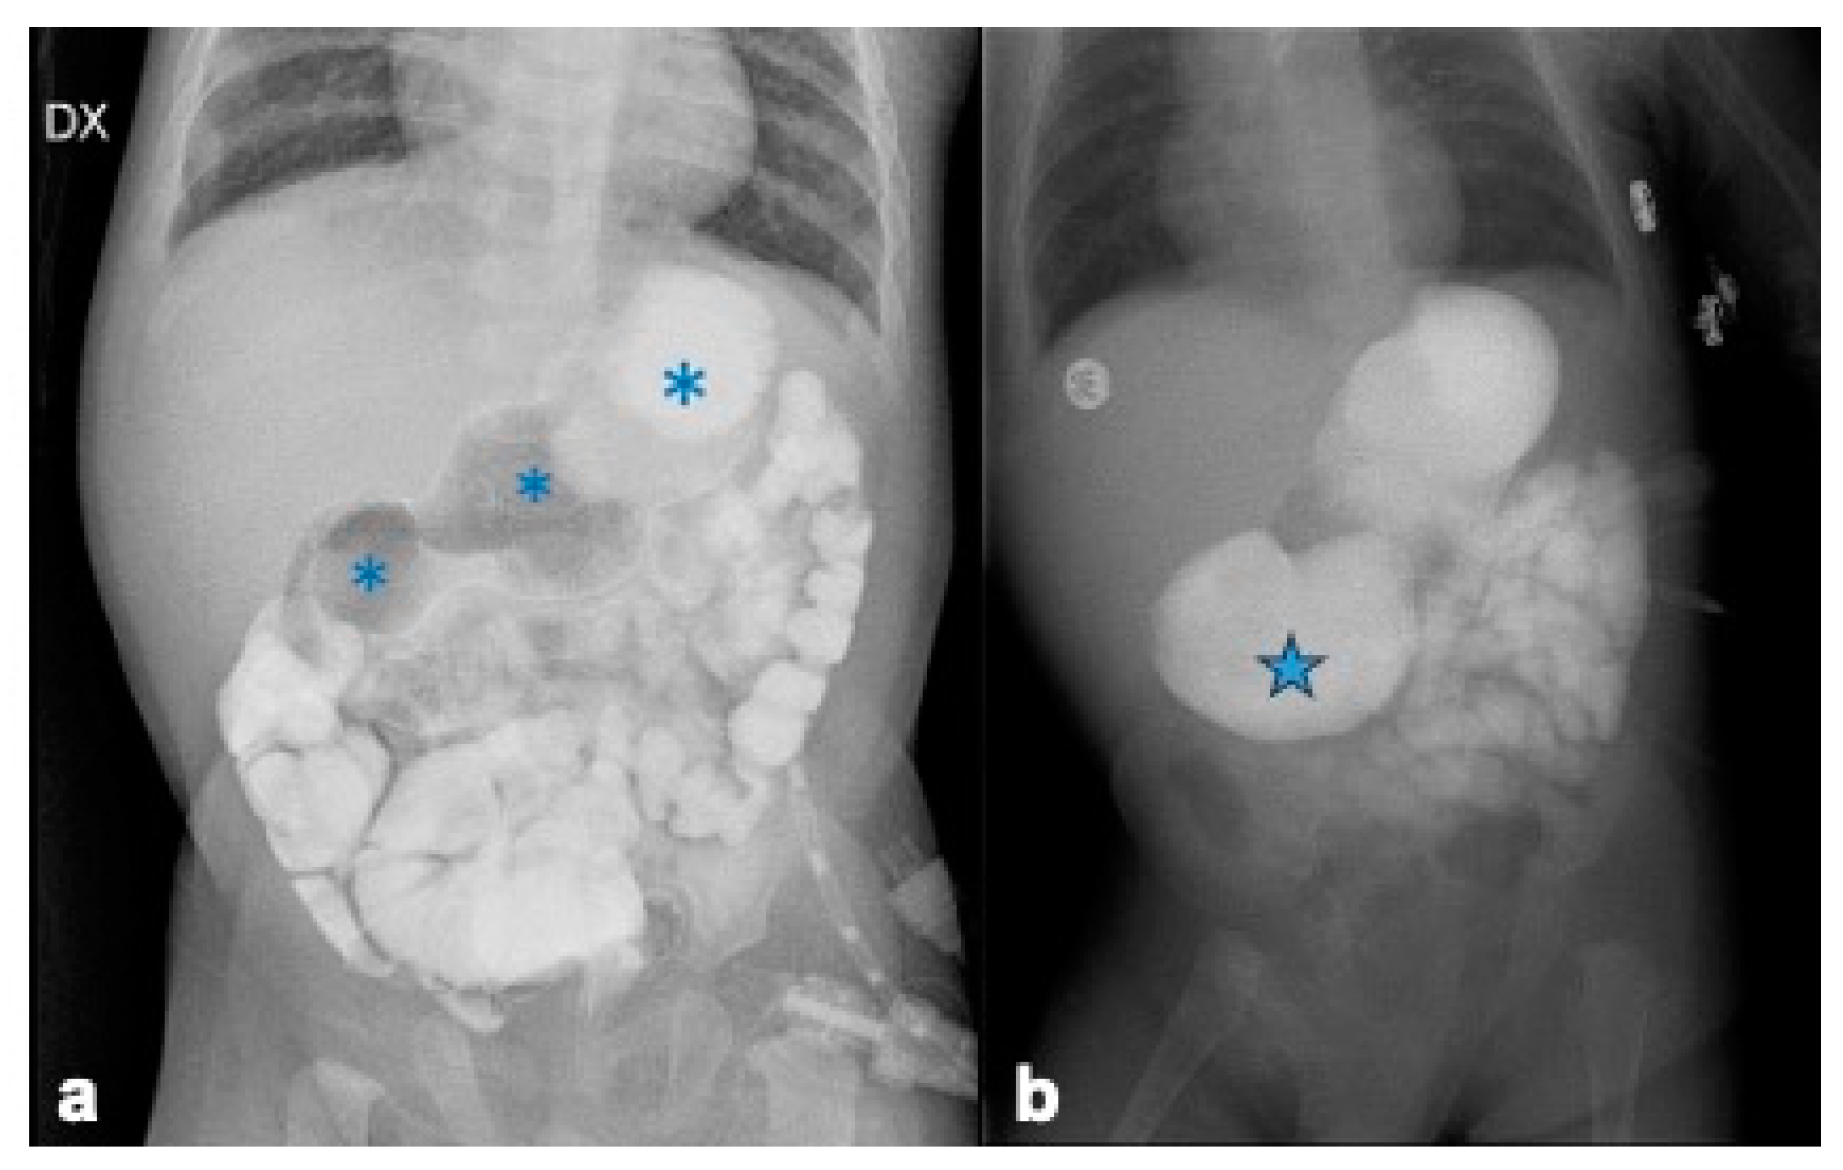

2.3. Investigations

2.4.3. Duodenal Web Localization